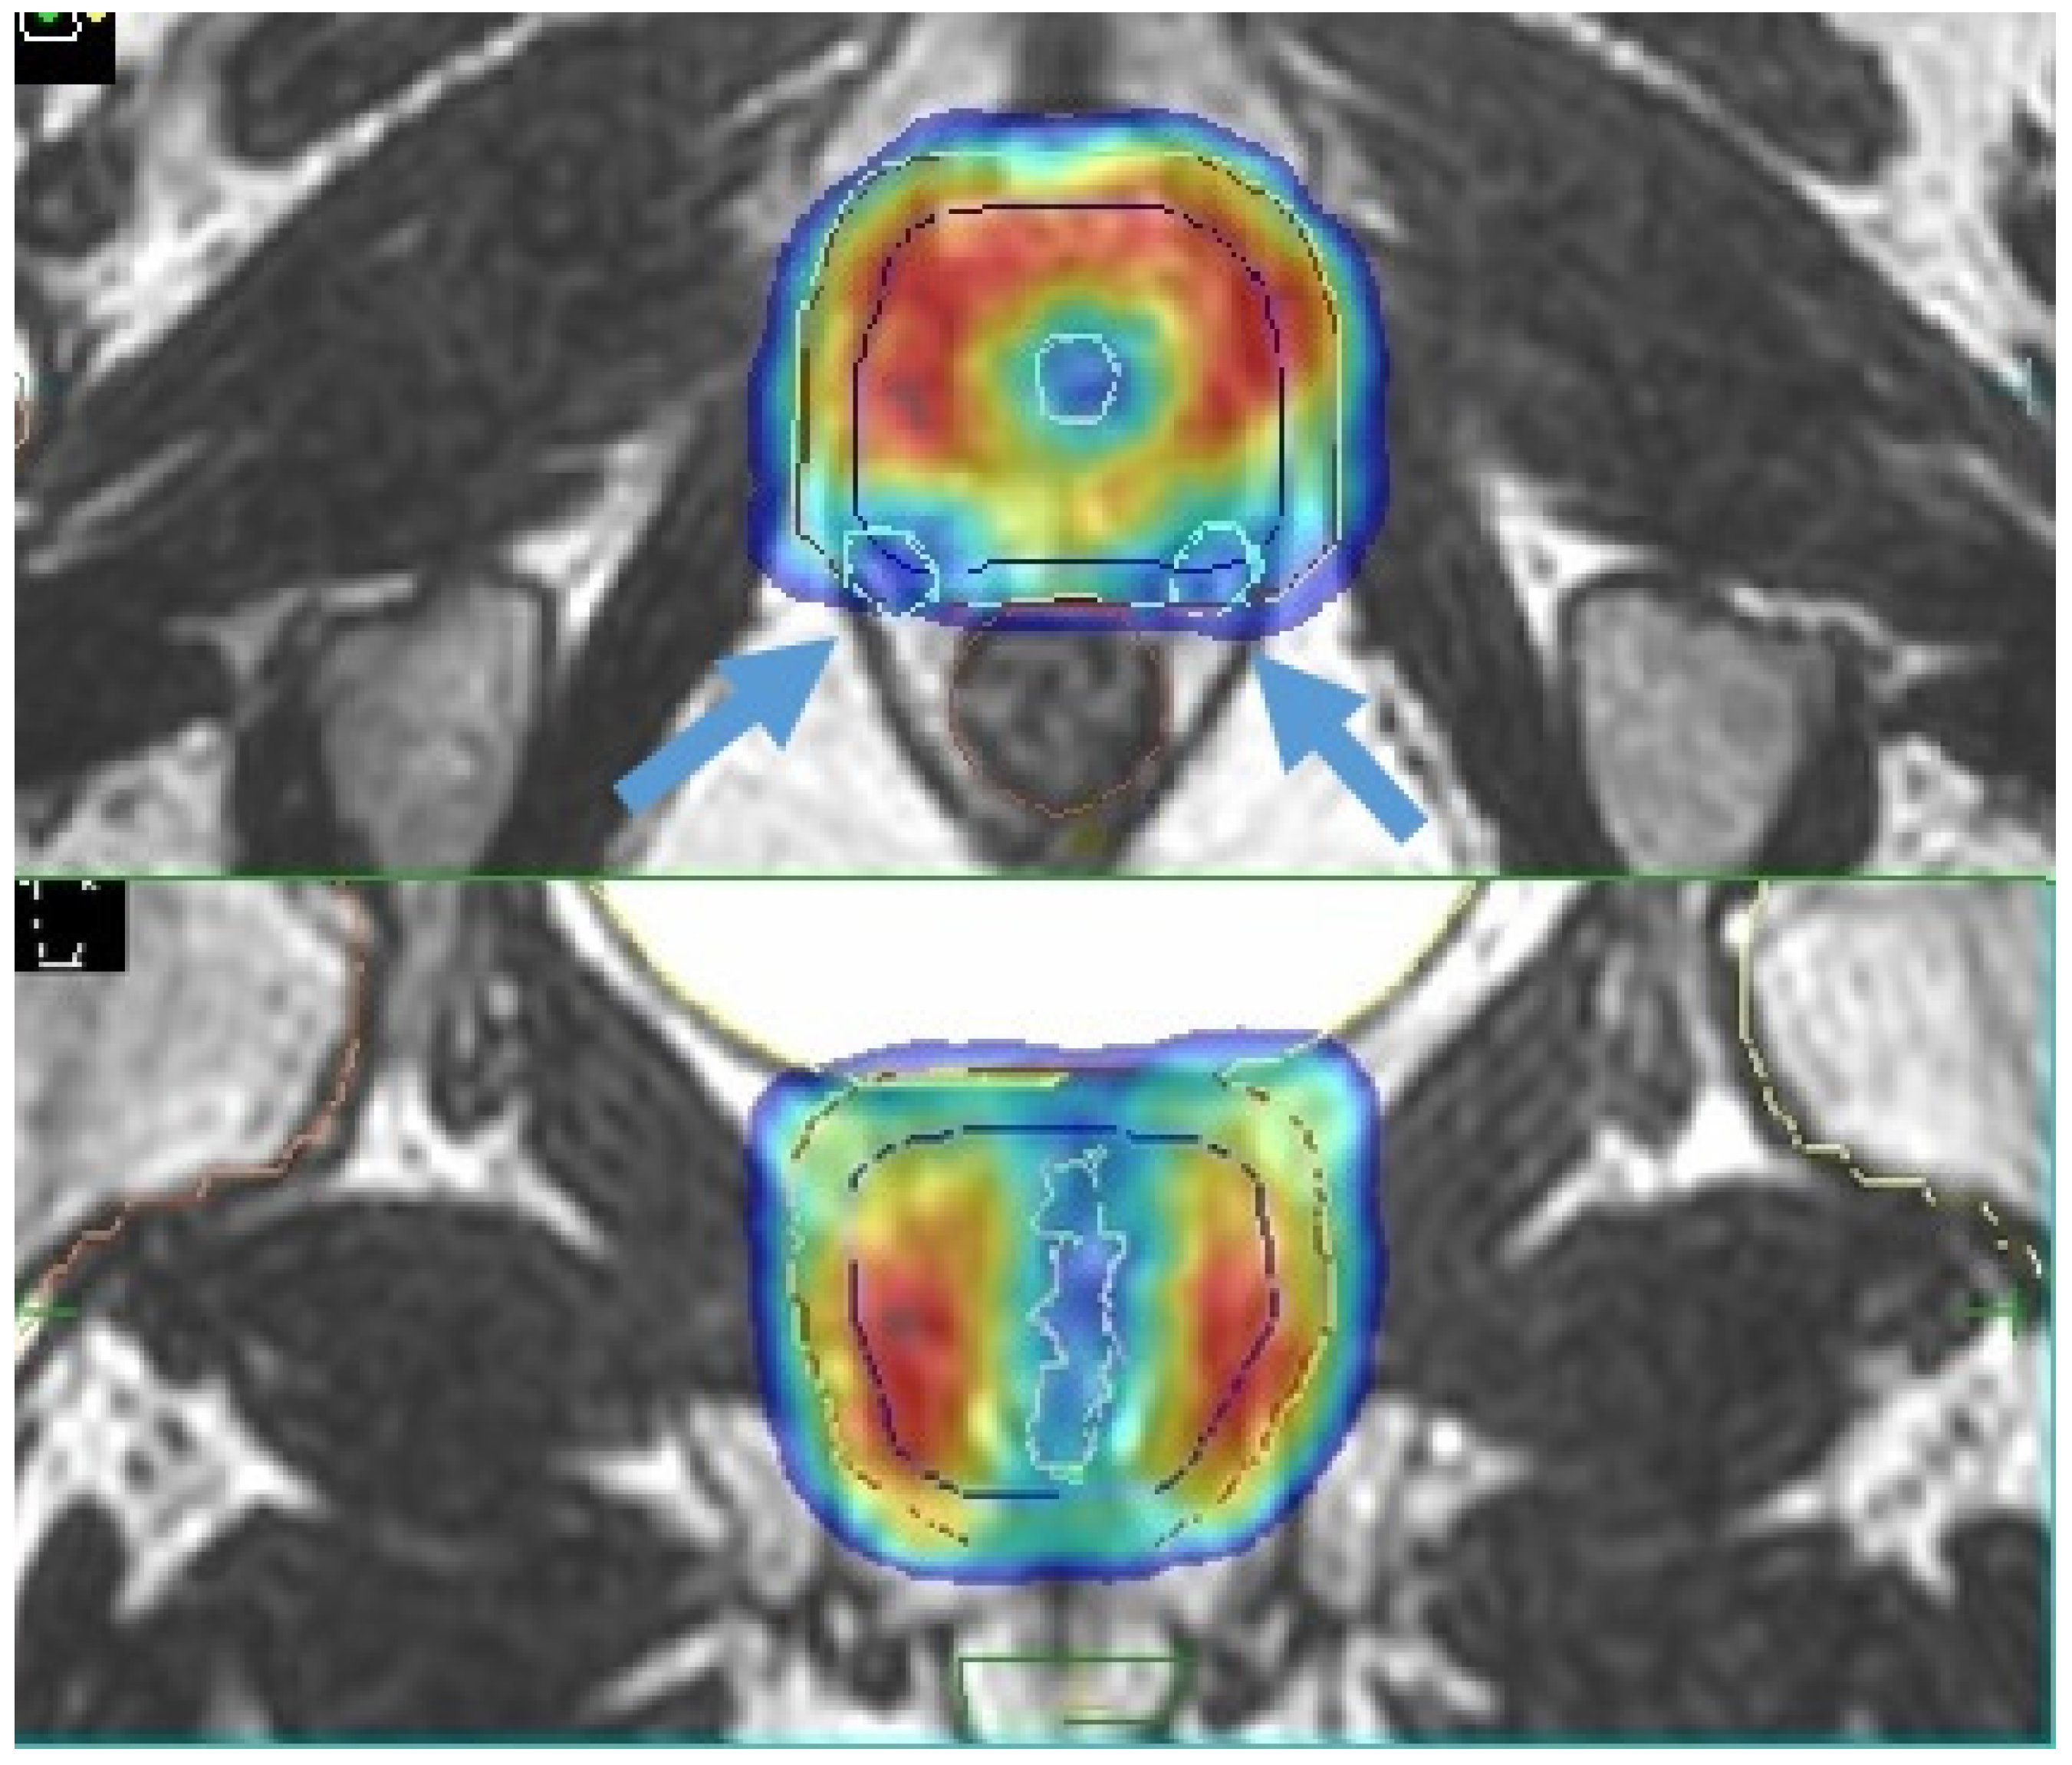

4.1. Boost of the Dominant Intraprostatic Lesion

- Cuccia, F.; Mazzola, R.; Nicosia, L.; Figlia, V.; Giaj-Levra, N.; Ricchetti, F.; Rigo, M.; Vitale, C.; Mantoan, B.; De Simone, A.; et al. Impact of hydrogel peri-rectal spacer insertion on prostate gland intra-fraction motion during 1.5 T MR-guided stereotactic body radiotherapy. Radiat. Oncol. 2020, 15, 1–9. [Google Scholar] [CrossRef] [PubMed]

- Ruggieri, R.; Rigo, M.; Naccarato, S.; Gurrera, D.; Figlia, V.; Mazzola, R.; Ricchetti, F.; Nicosia, L.; Giaj-Levra, N.; Cuccia, F.; et al. Adaptive SBRT by 1.5 T MR-linac for prostate cancer: On the accuracy of dose delivery in view of the prolonged session time. Phys. Med. 2020, 80, 34–41. [Google Scholar] [CrossRef] [PubMed]

- Alongi, F.; Rigo, M.; Figlia, V.; Cuccia, F.; Giaj-Levra, N.; Nicosia, L.; Ricchetti, F.; Sicignano, G.; De Simone, A.; Naccarato, S.; et al. 1.5 T MR-guided and daily adapted SBRT for prostate cancer: Feasibility, preliminary clinical tolerability, quality of life and patient-reported outcomes during treatment. Radiat. Oncol. 2020, 15, 1–9. [Google Scholar] [CrossRef]

- Alongi, F.; Rigo, M.; Figlia, V.; Cuccia, F.; Giaj-Levra, N.; Nicosia, L.; Ricchetti, F.; Vitale, C.; Sicignano, G.; De Simone, A.; et al. Rectal spacer hydrogel in 1.5T MR-guided and daily adapted SBRT for prostate cancer: Dosimetric analysis and preliminary patient-reported outcomes. Br. J. Radiol. 2021, 94, 20200848. [Google Scholar] [CrossRef] [PubMed]